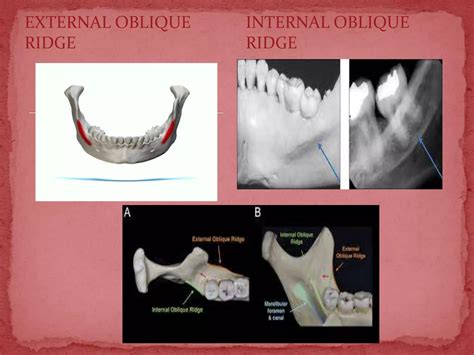

• submandibular fossa on pano

• mental foramen on x ray

• external oblique ridge on radiograph

• intra oral anatomy landmarks

• internal oblique ridge on xray

• external oblique ridge dental radiograph